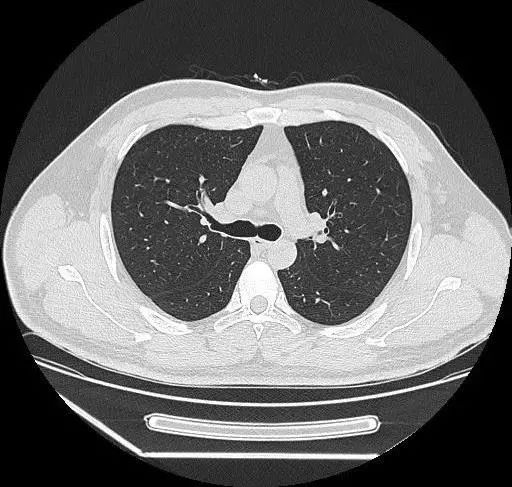

胸部:

肺、胸膜及纵隔的各种肿瘤、结核、炎症、支气管扩张、肺脓肿、肺不张、气胸、骨折、食道异物及各种变异等;